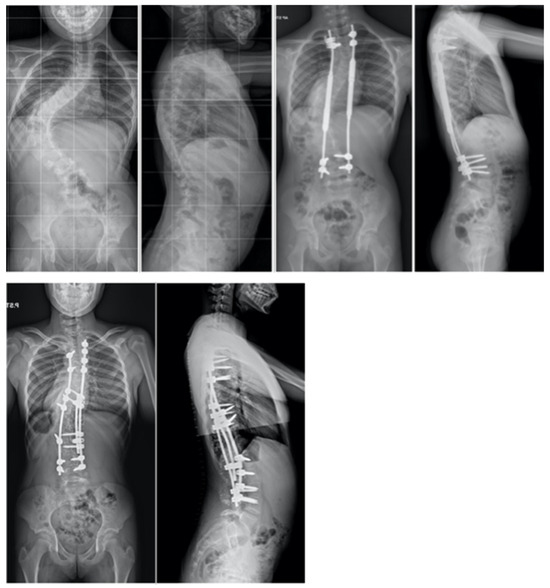

Surgical Treatment Strategies for Severe and Neglected Spinal Deformities in Children and Adolescents without the Use of Radical Three-Column Osteotomies

8. Temporary Internal Distraction Rods

9. MCGR as Temporary Internal Traction

10. Rib Resection/Thoracoplasty